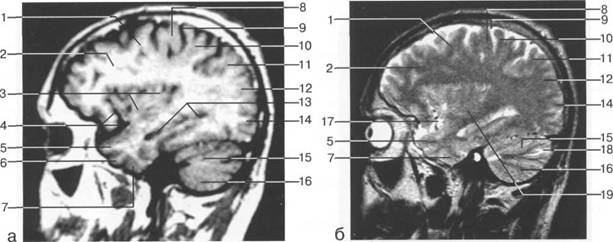

В латеральных отделах дно передней череп 13513u2010n 85;ой ямки образовано крышами глазниц, а в центральном - продырявленной пластинкой. Базальные отделы лобных долей представлены ко

ные извилины (рис. 1.10). Структуры средней череп 13513u2010n 85;ой ямки ограничены спереди малым крылом основной кости, снизу - большим крылом, сзади - передней поверхностью пирами «edge» «bone»

Содержимое средней череп 13513u2010n 85;ой ямки представлено базальными отделами височной доли.

цистерна четверохолмия; 14 -прямой синус; 15 -лобный рог; 16 - головка хвостатого ядра; 17 -перед

III ди зрительного бугра идет ретроталамическая цистерна, ориентированная во фронтальной